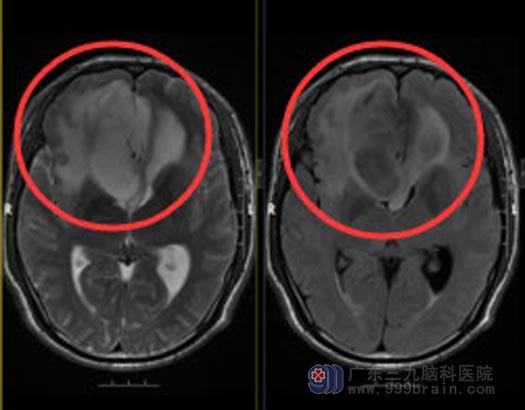

杨先生头痛头晕一个多月,在广东三九脑科医院查出颅内有7.1cm×6.3cm×4.8cm的巨大肿瘤,位于双侧额部、胼胝体部,考虑胶质瘤。